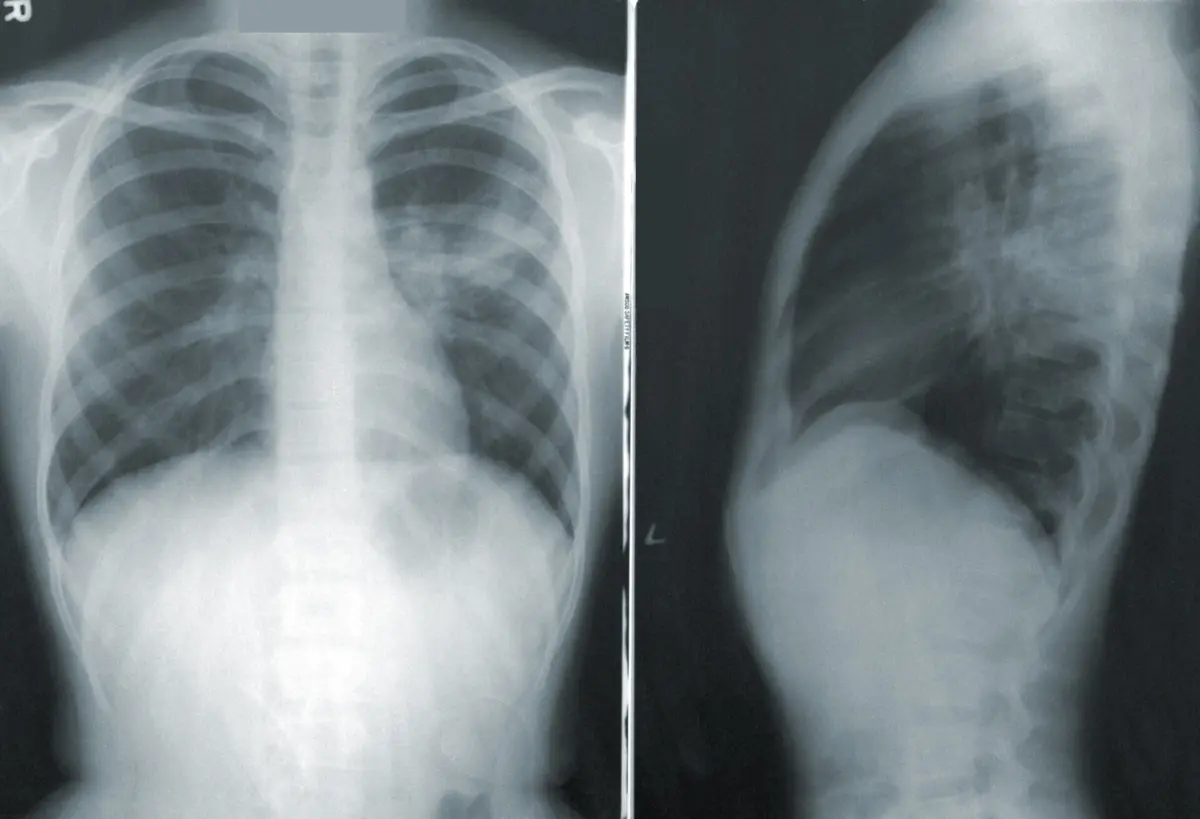

Tabagismo responsável pela maioria dos casos

Anunciado no final de 2022 pelo então ministro da Saúde Manuel Pizarro, o rastreio do cancro do pulmão estará prestes a sair do plano das ideias. Ao JN, a Direção-Geral da Saúde (DGS) revela estar a selecionar os prestadores, estimando que os primeiros projetos-piloto arranquem ainda durante este ano. De acordo com a literatura, o rastreio permite um aumento de diagnósticos em estádios precoces, podendo reduzir a mortalidade por cancro do pulmão em mais de 20%.

Neoplasia que é a primeira causa de morte por cancro em Portugal, respondendo, em 2023, por 3,8% da mortalidade total. No despacho de nomeação do referido grupo de trabalho, a DGS lembrava que “os potenciais benefícios do diagnóstico precoce do cancro do pulmão através do rastreio por tomografia computorizada de baixa dose poderão ser cerca de 12,5 anos de vida adicional”.